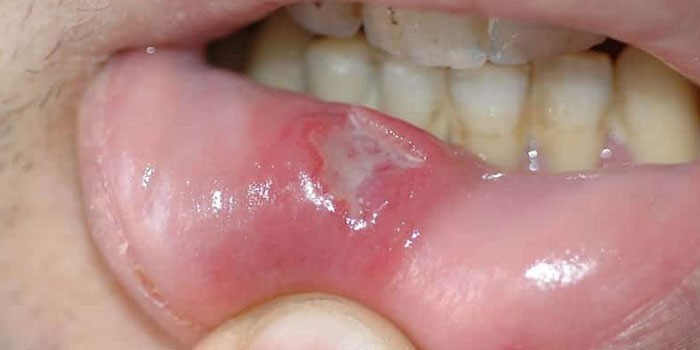

Язвочки в ротовой полости – это круглые или овальные ранки, которые возникают на щеках, губах, языке. Они могут быть белого, красного, желтого или серого цвета. Часто это единичные образования, но иногда наблюдают несколько ранок. Некоторые болячки выпуклые и заполнены жидкостью, похожи на волдыри.

Важно: язвы во рту не нужно путать с герпесом, появление которого сопровождают пузырьки в районе губ. Эта болезнь начинается с покалывания, зуда или жжения. Подобными симптомами появление язв во рту не сопровождается. Тем не менее герпес может стать причиной стоматита.